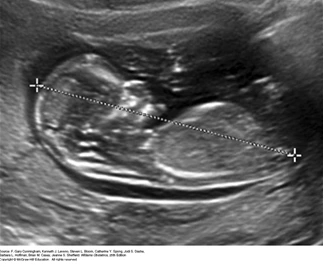

두둔장.PNG 윌리엄스 산과학 25th, ch5. 머리엉덩이 길이

임신 6-8주 차에 아기의 머리에서 엉덩이까지의 길이를 재서 임신 몇 주인지 아기가 언제 태어날지를 확인합니다.

이 외에도, 아기의 머리 둘레와 배 둘레, 허벅지 뼈 길이, 예상 몸무게 등을 초음파로 확인합니다.